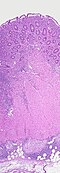

U svrhu potvrđivanja dijagnoze se, tijekom kolonoskopije često uzimaju biopsije debelog crijeva . Neke karakteristične patološke promjene koje se pronalaze mikroskopskom pretragom ukazuju na Crohnovu bolest. Jedna od njih je transmuralna upala, što znači da se upalne promjene protežu kroz cijelu debljinu stijenke crijeva.[1] U aktivnom stadiju bolesti nalaze se i ulceracije. Između dijelova crijeva zahvaćenih bolešću i susjednih dijelova crijeva granica je jasna – što je karakteristični znak i naziva se preskačućim lezijama. Mikroskopskom pretragom se u tkivu crijeva uzetog biopsijom nalaze upalne promjene u sluznici, obilježene žarišnim nakupljanjem neutrofila (vrste upalnih stanica) unutar epitela. Do ovog nakupljanja tipično dolazi u područjima kojima podleže nakupine limfatičnog tkiva. Neutrofili, zajedno s limfocitima, mogu infiltrirati Lieberkuhnove kripte, što se naziva kriptapscesima. Nakupine promijenjenih makrofaga, zbog svoje sličnosti s epitelnim stanicama zvanih epiteloidne stanice koje se nalaze u oko 50% slučajeva Crohnove bolesti nazivaju se granulomi. Epiteloidne se stanice mogu međusobno stapati, tvoreći divovske stanice s više jezgara. Granulomi su najkarakterističniji nalaz u Crohnovoj bolesti. U ovoj bolesti oni ne sadrže središnju “kazeoznu” nekrozu (koja je tako nazvana zbog svog makroskopskog izgleda sličnog svježem, kravljem siru), a koja se ponajprije nalazi kod upala obilježenih stvaranjem granuloma, kao što je tuberkuloza. U biopsijama se mogu naći znakovi kroničnog oštećenja sluznice, poput sniženja i zaravnjenja crijevnih resica u tankome crijevu i nepravilnog grananja kripta.[85][86]